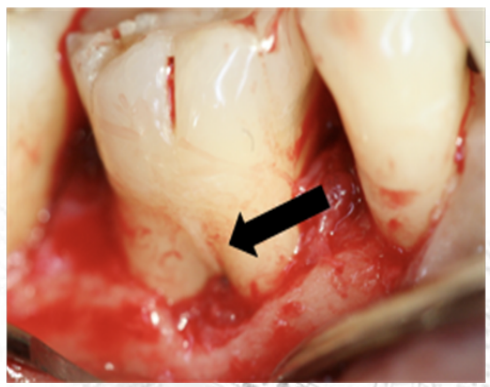

Palatogingival Groove (PGG)